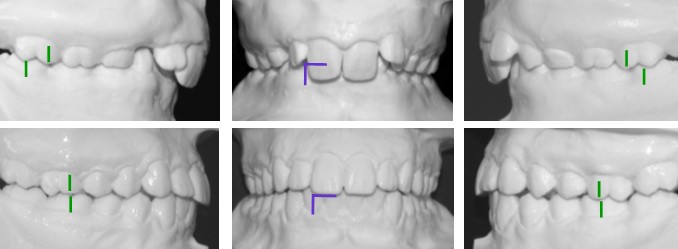

ก่อนเข้ารับการรักษา

หลังได้รับการรักษา

ผู้ป่วยภาวะฟันสบเหลื่อมชนิด Class II Division II Overbite เมื่อได้รับการรักษาหายดีแล้วมีโอกาสฟันเคลื่อนกลับตำแหน่งเดิมได้สูง ดังนั้นจึงจำเป็นต้องเริ่มต้นทำการรักษาตั้งแต่เนิ่นๆ (การรักษาแบบหลายขั้นตอน) และต้องใช้เครื่องมือจัดฟันที่มีประสิทธิภาพสูง (เทคนิคของ Wilson) จากการใช้แผนการรักษาของเรา เป็นที่น่ายินดีอย่างยิ่งที่พบว่าผู้ป่วยมีฟันเคลื่อนที่กลับตำแหน่งเดิมน้อยมาก

ขณะเข้ารับการรักษา ผู้ป่วยอายุ 11 ปี มีขากรรไกรล่างที่หลุบถอยไปด้านหลังอย่างมาก และถูกฟันหน้าบนกลางที่งุ้มเข้าครอบปิดทั้งหมด จะมองไม่เห็นฟันตัดล่างเพราะมีภาวะสบลึก กระดูกขากรรไกรบนและล่างเล็กอันจะสังเกตได้จากฟันหน้าบนและล่างซ้อนเกอย่างเห็นได้ชัด

ผู้ป่วยมีภาวะฟันสบเหลื่อมชนิด Class II Division II Overbite ได้รับการรักษาแบบหลายขั้นตอน ในขั้นแรกใช้เครื่องมือกระตุ้นแอกติเวเตอร์ KI II 2 และต่อมาใช้เครื่องกระตุ้นเพื่อจัดฟันแบบของ Prof. Sander (VDP) และเครื่องมือจัดฟันชนิดติดแน่น โดยใช้เครื่องมือจัดฟันชนิดถอดได้นาน 23 เดือน และเครื่องมือชนิดติดแน่น 17 เดือน